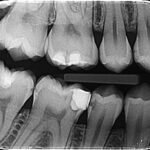

Primjer bitewing snimke

• Za razliku od panoramskih snimaka (koji prikazuju cijelu čeljust), bitewing snimke fokusiraju se na manji dio usta i pružaju detaljniji prikaz zuba i međuzubnih prostora.

• U usporedbi s periapikalnim snimkama (koje pokazuju cijeli zub, uključujući korijen), bitewing snimke prikazuju samo krune i dio korijena.